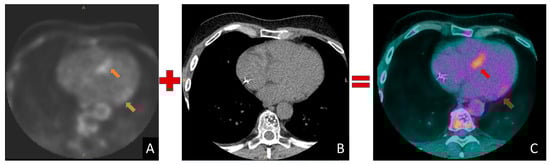

4.5. Senior Athlete with Unexplained Myocardial Hypertrophy and Suspected Cardiac Amyloidosis